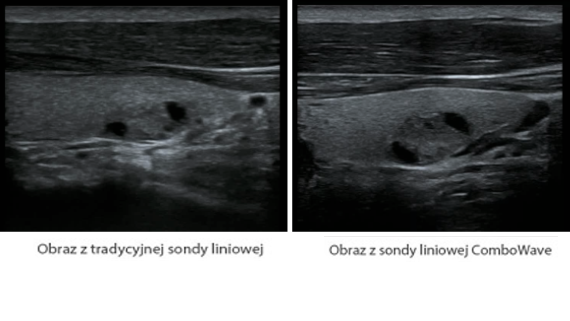

X-Insight to rozwi?zanie umo?liwiaj?ce wnikliw? analiz?, zapewniaj?c bardziej szczeg├│?owy obraz.

Opieraj?c si? na analizie potrzeb klienta, DC-60 Exp X-Insight zosta? zaprojektowany tak, aby znacznie usprawni? diagnostyk?, kt├│ra jest wspomagana przez technologi? eXpress Clarity, eXceptional Intelligence i eXceeding Experience.

Sondy